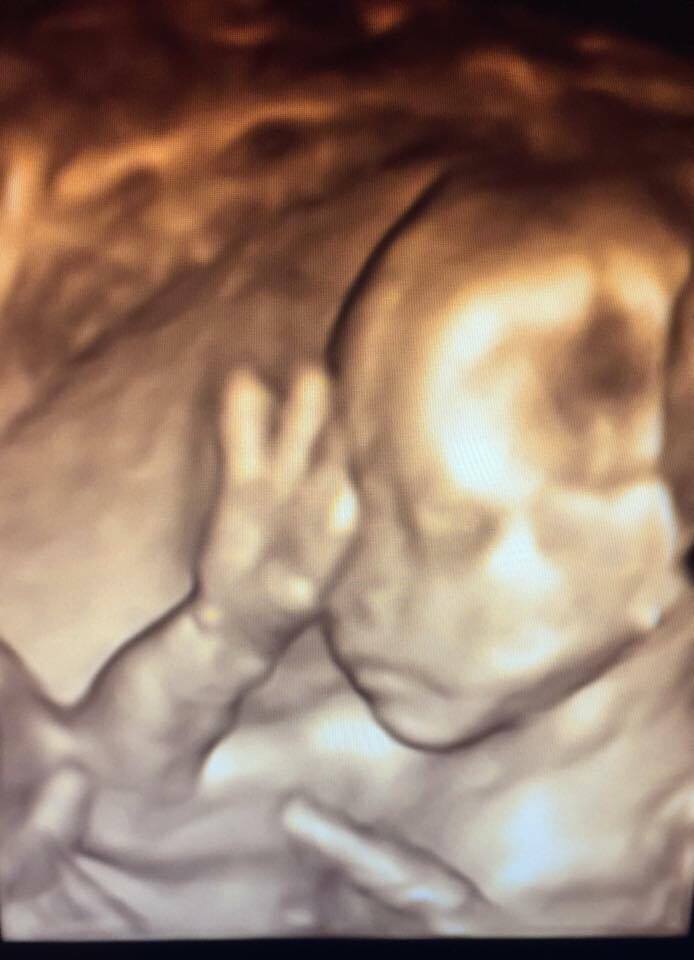

寶寶吃手指(上圖)、寶寶揉眼睛(下圖)。動作表情已很豐富。圖/作者提供